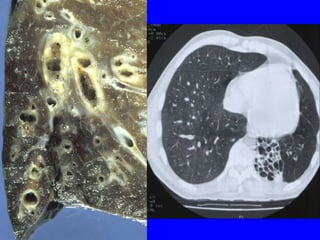

Bronchiectasis

Gross

• Distended peripheral

bronchi (Due to weakening

of wall)

• Bronchiectasis

• Infection + permanent dilatation of bronchi

• Causes:

• infections and causes of bronchial obstruction

(FB, mucus plugs, tumors, sequestrations, cystic fibrosis)

• immotile cilia (Kartagener’s )syndrome

(Bronchiectasis, dextrocardia -situs inversus, chronic

sinusitis, and infertility)

• Clinically:

• Chronic cough, productive of purulent sputum

• Dyspnea and orthopnea in severe cases

• later obstructive respiratory insufficiency & Corpulmonale